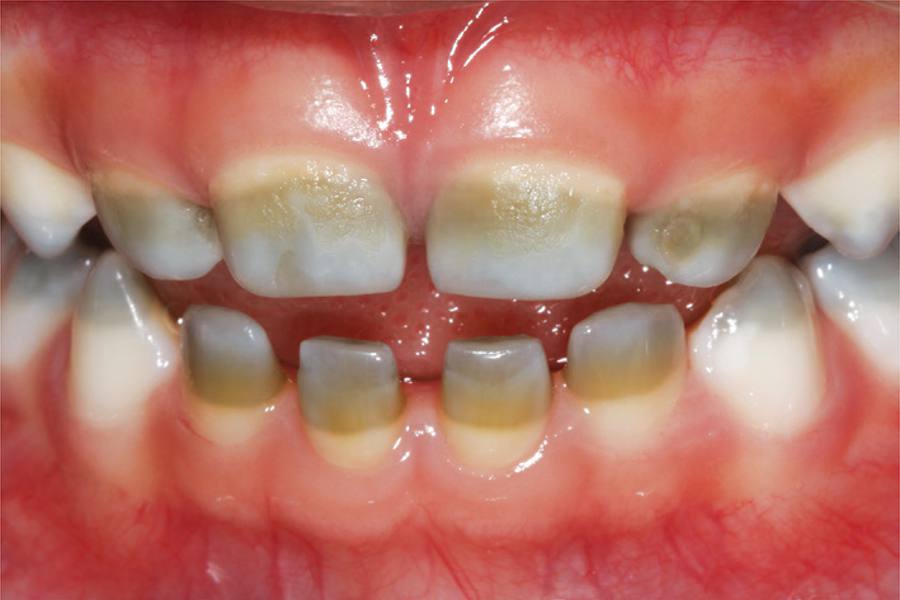

Alteração cromática dentária decorrente de colestase neonatal

A colestase resulta da redução da síntese dos ácidos biliares ou do bloqueio (intra ou extra-hepático) da excreção dos componentes biliares (colesterol, fosfolipídeos, sais biliares, bilirrubina e proteínas) para o intestino delgado. O recém-nascido, em especial o pré-termo, tem predisposição à colestase neonatal, em virtude da imaturidade hepática. Esta pode gerar problemas sistêmicos, como colúria, acolia fecal, hipercolesterolemia e hiperbilirrubinemia.(,) Também pode gerar alterações na composição estrutural ou na espessura dos tecidos mineralizados dos dentes em formação e alterações cromáticas intrínsecas, decorrentes da hiperbilirrubinemia (concentração de bilirrubina total no soro sanguíneo superior a 5mg/dL).() Em altas concentrações, a bilirrubina deposita-se no esmalte e/ou na dentina durante o período de mineralização, alterando sua coloração de forma permanente,(-) pois esses tecidos, depois da maturação, perdem sua atividade metabólica.()

Paciente do sexo feminino, 2 anos de idade, compareceu à clínica de odontopediatria da Faculdade de Odontologia de Araraquara da Universidade Estadual Paulista “Júlio de Mesquita Filho” (UNESP), acompanhada pelo pai, com queixa de dentes manchados. Na anamnese, foi constatado que a criança nasceu na 29ª semana de gestação, pesando 1,8kg e com índice de Apgar 2 no primeiro minuto e 4 no quinto minuto, necessitando de medidas urgentes de reanimação. Apresentou ainda hipóxia, colestase neonatal, persistência do canal arterial (PCA), comunicação interventricular (CIV), anemia e sepse. Permaneceu na unidade de terapia intensiva (UTI) por 40 dias, onde foi submetida à fototerapia de alta intensidade, aliada a medicamentos para redução da produção de bilirrubina. O tratamento prosseguiu até a normalização do quadro. Exames realizados aos 3 meses de vida mostraram concentração de bilirrubina total igual a 14,9mg/dL; transaminase glutâminco oxalacética (TGO) de 178U/L e transaminase glutâmico prúvica (TGP) de 165U/L. Com 1 ano de idade, estas mostraram-se dentro dos padrões de referência, e a criança não apresentava sequelas motoras e nem intelectuais tardias.